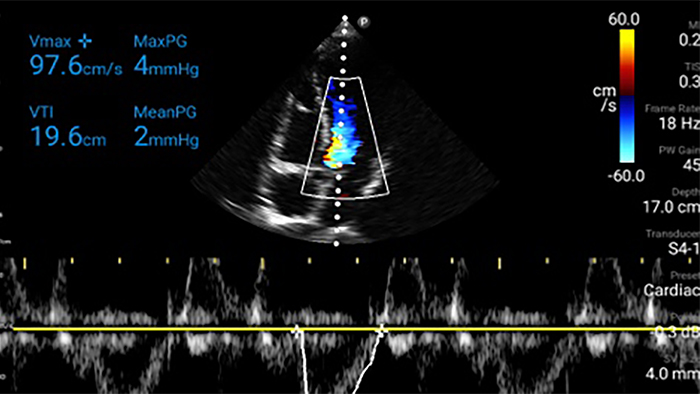

• Rozszerzony zakres częstotliwości roboczej od 4 do 1 MHz • Obrazowanie 2D, kolorowy Doppler, tryb M-mode, zaawansowana technika XRES oraz wielowymiarowe obrazowanie harmoniczne • Obrazowanie w wysokiej rozdzielczości do badań jamy brzusznej i serca: optymalizacja predefiniowanych ustawień badań serca, położniczo-ginekologicznych, płuc, jamy brzusznej oraz FAST.